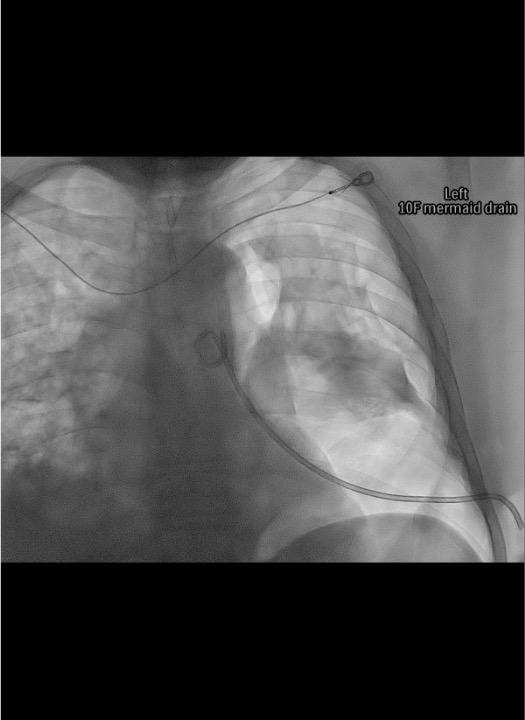

- Pleural fluid (gravity-dependent): Enter posterolateral at 4th–5th ICS posterior axillary line; orient tube posteroinferiorly. In supine patient, fluid collects posteriorly. Guide tip toward spine on AP fluoro, confirm stays close to spine on oblique view.

Catheter placement

Connect and confirm

Post-placement CXR